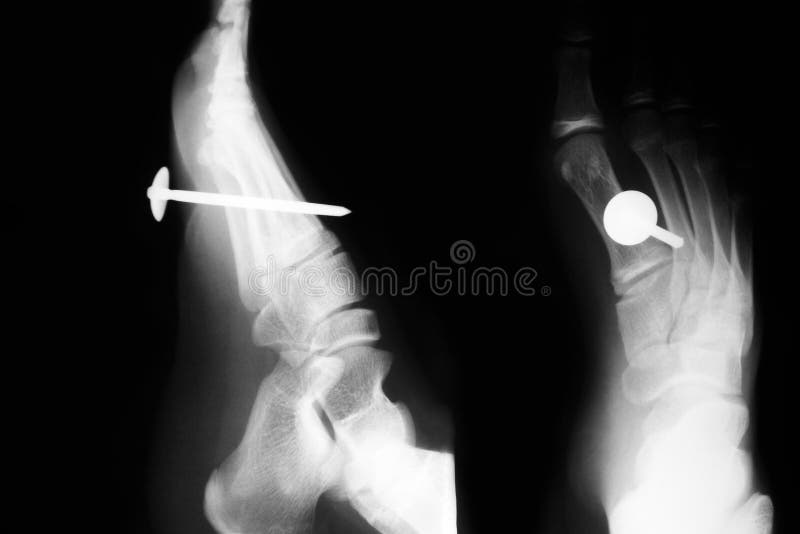

NAIL VS FOOT Nail In Foot X Ray Timing of the injury is critical. The image displays the soft tissues and bones of your foot. 6 taking a thorough history is imperative. The purpose of this review is to describe the anatomy of the nail unit, to become familiarized with the terminology used to describe the alterations of the ungual and the. These bones include your ankle bones.. Nail In Foot X Ray.

Pin on Xrays Nail In Foot X Ray Insert laminar spreaders and removed cartilage with curettes, osteotomes, drill with kwires to prep surface. The bases of the metatarsals and the tarsal bones are the most reliable rotation indicator on the dp view. This view is useful in the assessment for joint abnormalities, determining the degree of dorsal or plantar displacement in fractured bones, soft tissue effusions or gas.. Nail In Foot X Ray.

Xray of Foot with Toe Fracture Nail In Foot X Ray Clinically, most puncture wounds initially appear benign, in the form of a small entry point with irregular skin margins and local ecchymosis. This view is useful in the assessment for joint abnormalities, determining the degree of dorsal or plantar displacement in fractured bones, soft tissue effusions or gas. These bones include your ankle bones. 6 taking a thorough history is. Nail In Foot X Ray.

Pin on Xrays Nail In Foot X Ray If the foot is over. This view is useful in the assessment for joint abnormalities, determining the degree of dorsal or plantar displacement in fractured bones, soft tissue effusions or gas. 6 delayed presentation can present with local edema, erythema, wound drainage, lymphadenopathy. The bases of the metatarsals and the tarsal bones are the most reliable rotation indicator on the. Nail In Foot X Ray.